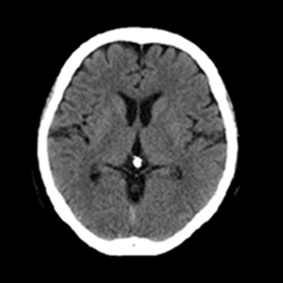

CT検査とは多方向からX線を照射し、身体の断面を撮影する検査です。

また、撮影した画像を重ね合わせることにより立体画像を構築し、より細かい診断ができます。